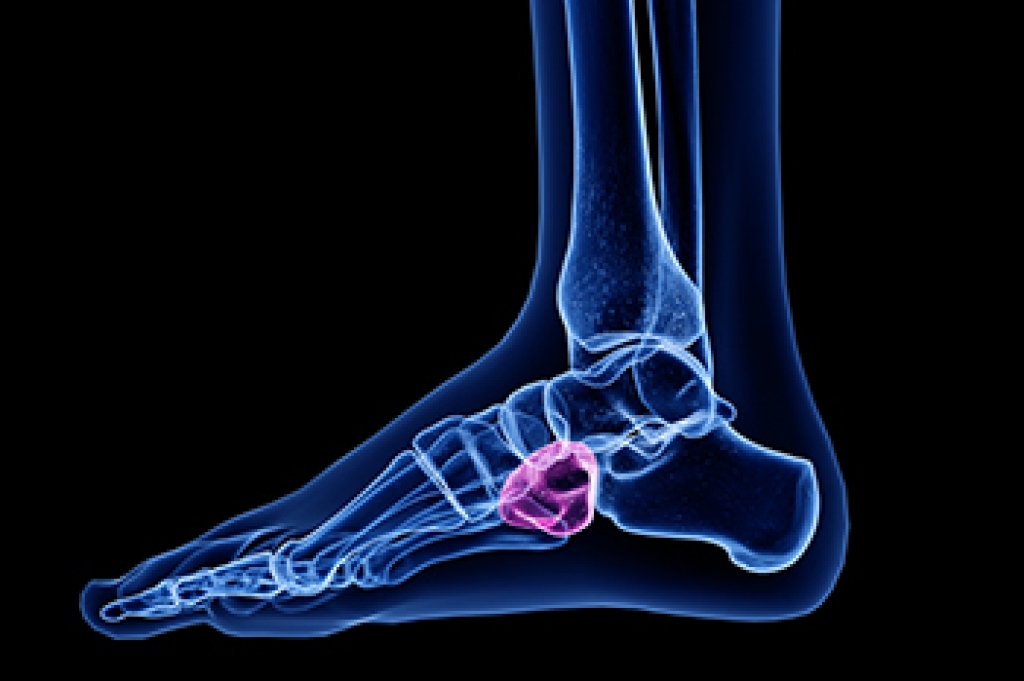

- Removing foot deformities like bunions and bone spurs

- Severe arthritis that has caused bone issues

- Bunionectomy for painful bunions

- Surgical fusion for realignment of bones